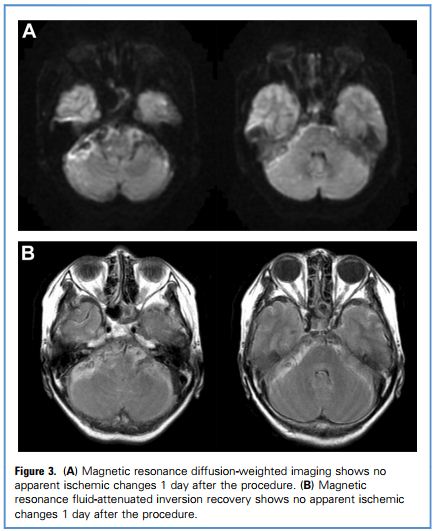

术后患者无任何神经系统体征,术后第1天头颅MRI检查正常,未见缺血病灶。